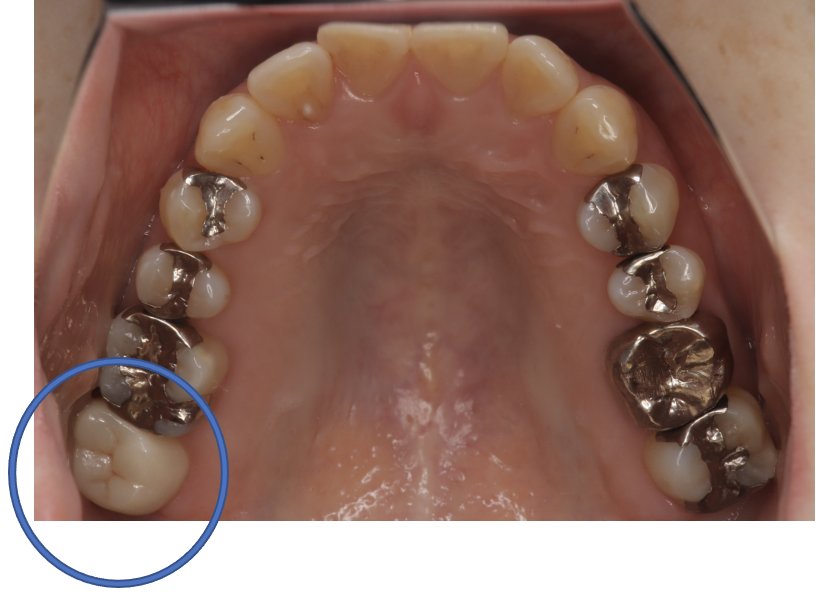

フルジルコニアCr 25 No.56

After

| 備考 | 院長より 銀歯の内部に虫歯が進行してしまっていたケースです。中を開けて見てみると、外から想像するよりもはるかに虫歯が広がってしまっていました。幸運にも神経を保存できたので、生きた臓器としてまだ使うことが可能です。残存歯質がかなり薄く弱くなってしまったので、ジルコニアで被せて守ってあげています。しっかりとした治療ができたので、まだまだ長く使っていけるでしょう。 |